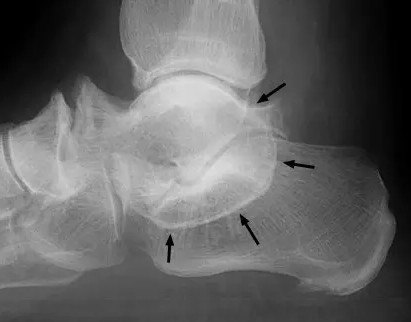

本征象用于描述跟骨距骨桥(或称跟距融合)的平片侧位表现,正位表现为

距骨后方,见于5-15%的正常人

跟距骨桥的微创治疗(关节镜下切除术)